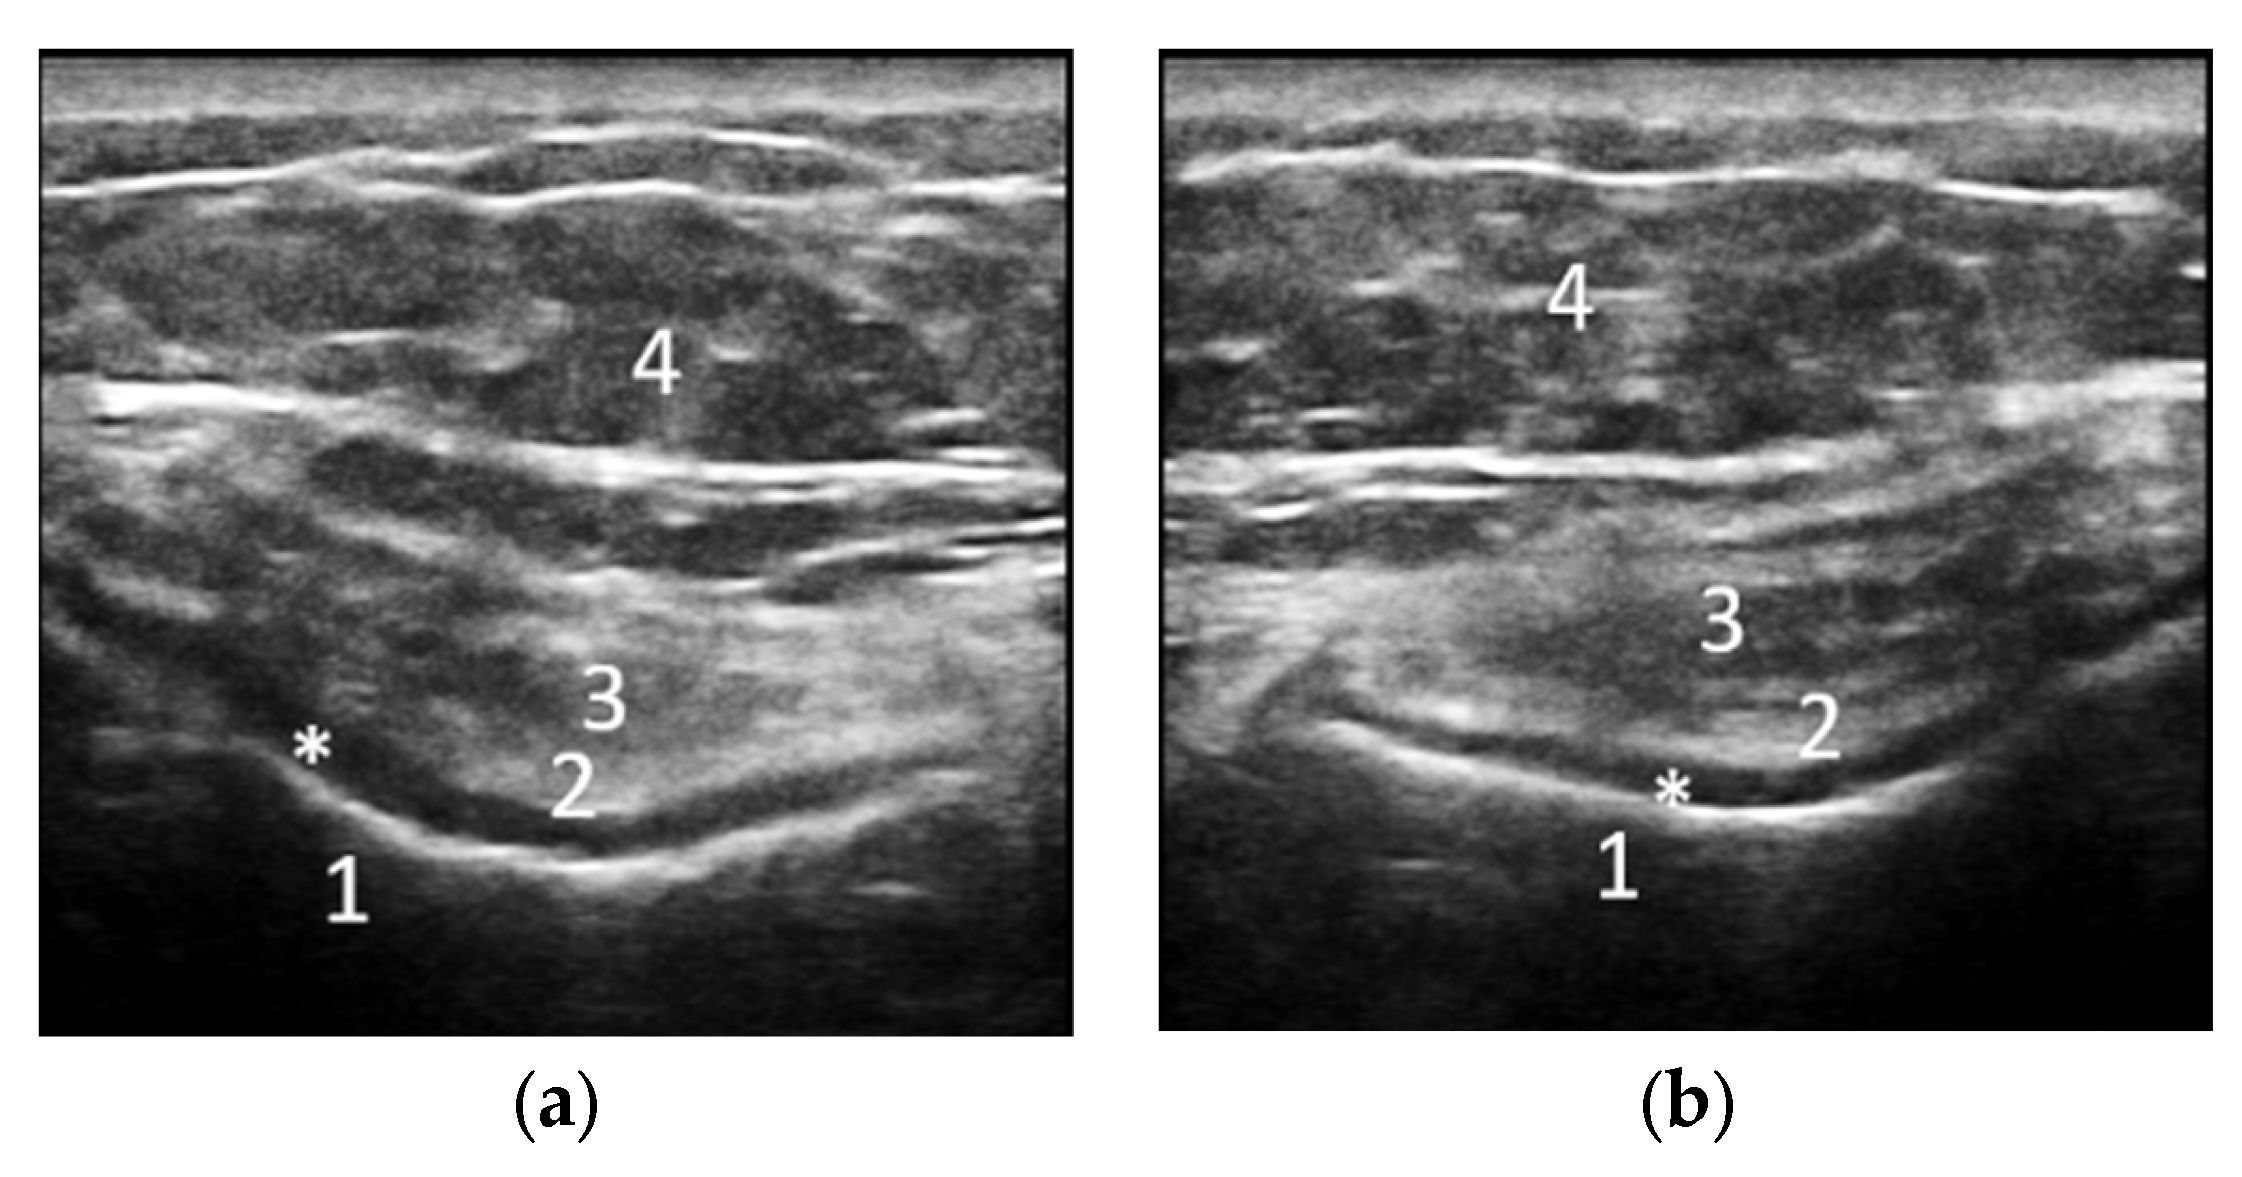

2.2. Demographic Characteristics and Assessment of Clinical, Laboratory and Imaging Data